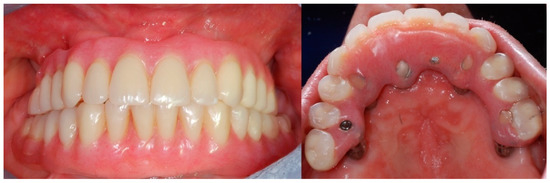

2. Case Report